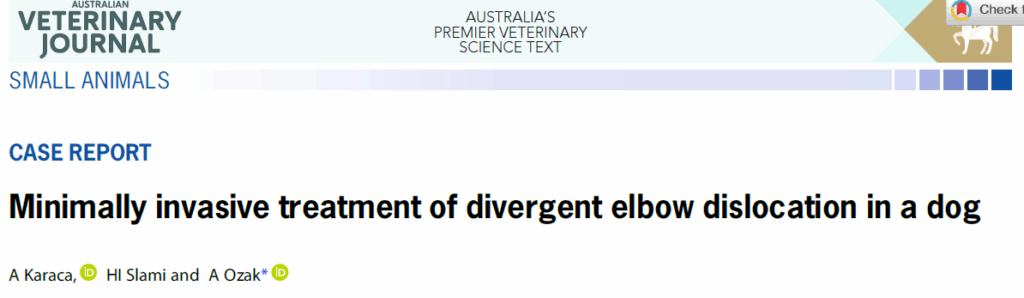

X光显示右前臂呈现前后方向的肘关节脱位。正侧位X光片中,肱骨位于桡骨和尺骨之间,因此该脱位可被定义为前后方向的肘关节脱位。头尾位X光片肘关节不匹配(下图)。

↑ 犬右肘关节的正侧位和头尾位X光片,显示前后方向的肘关节脱位。 (A) 正侧位显示桡骨头向前上方移位,尺骨鹰嘴向后下方移位,两者均被肱骨髁远端分隔。 (B) 头尾位X光片显示肘关节不匹配。